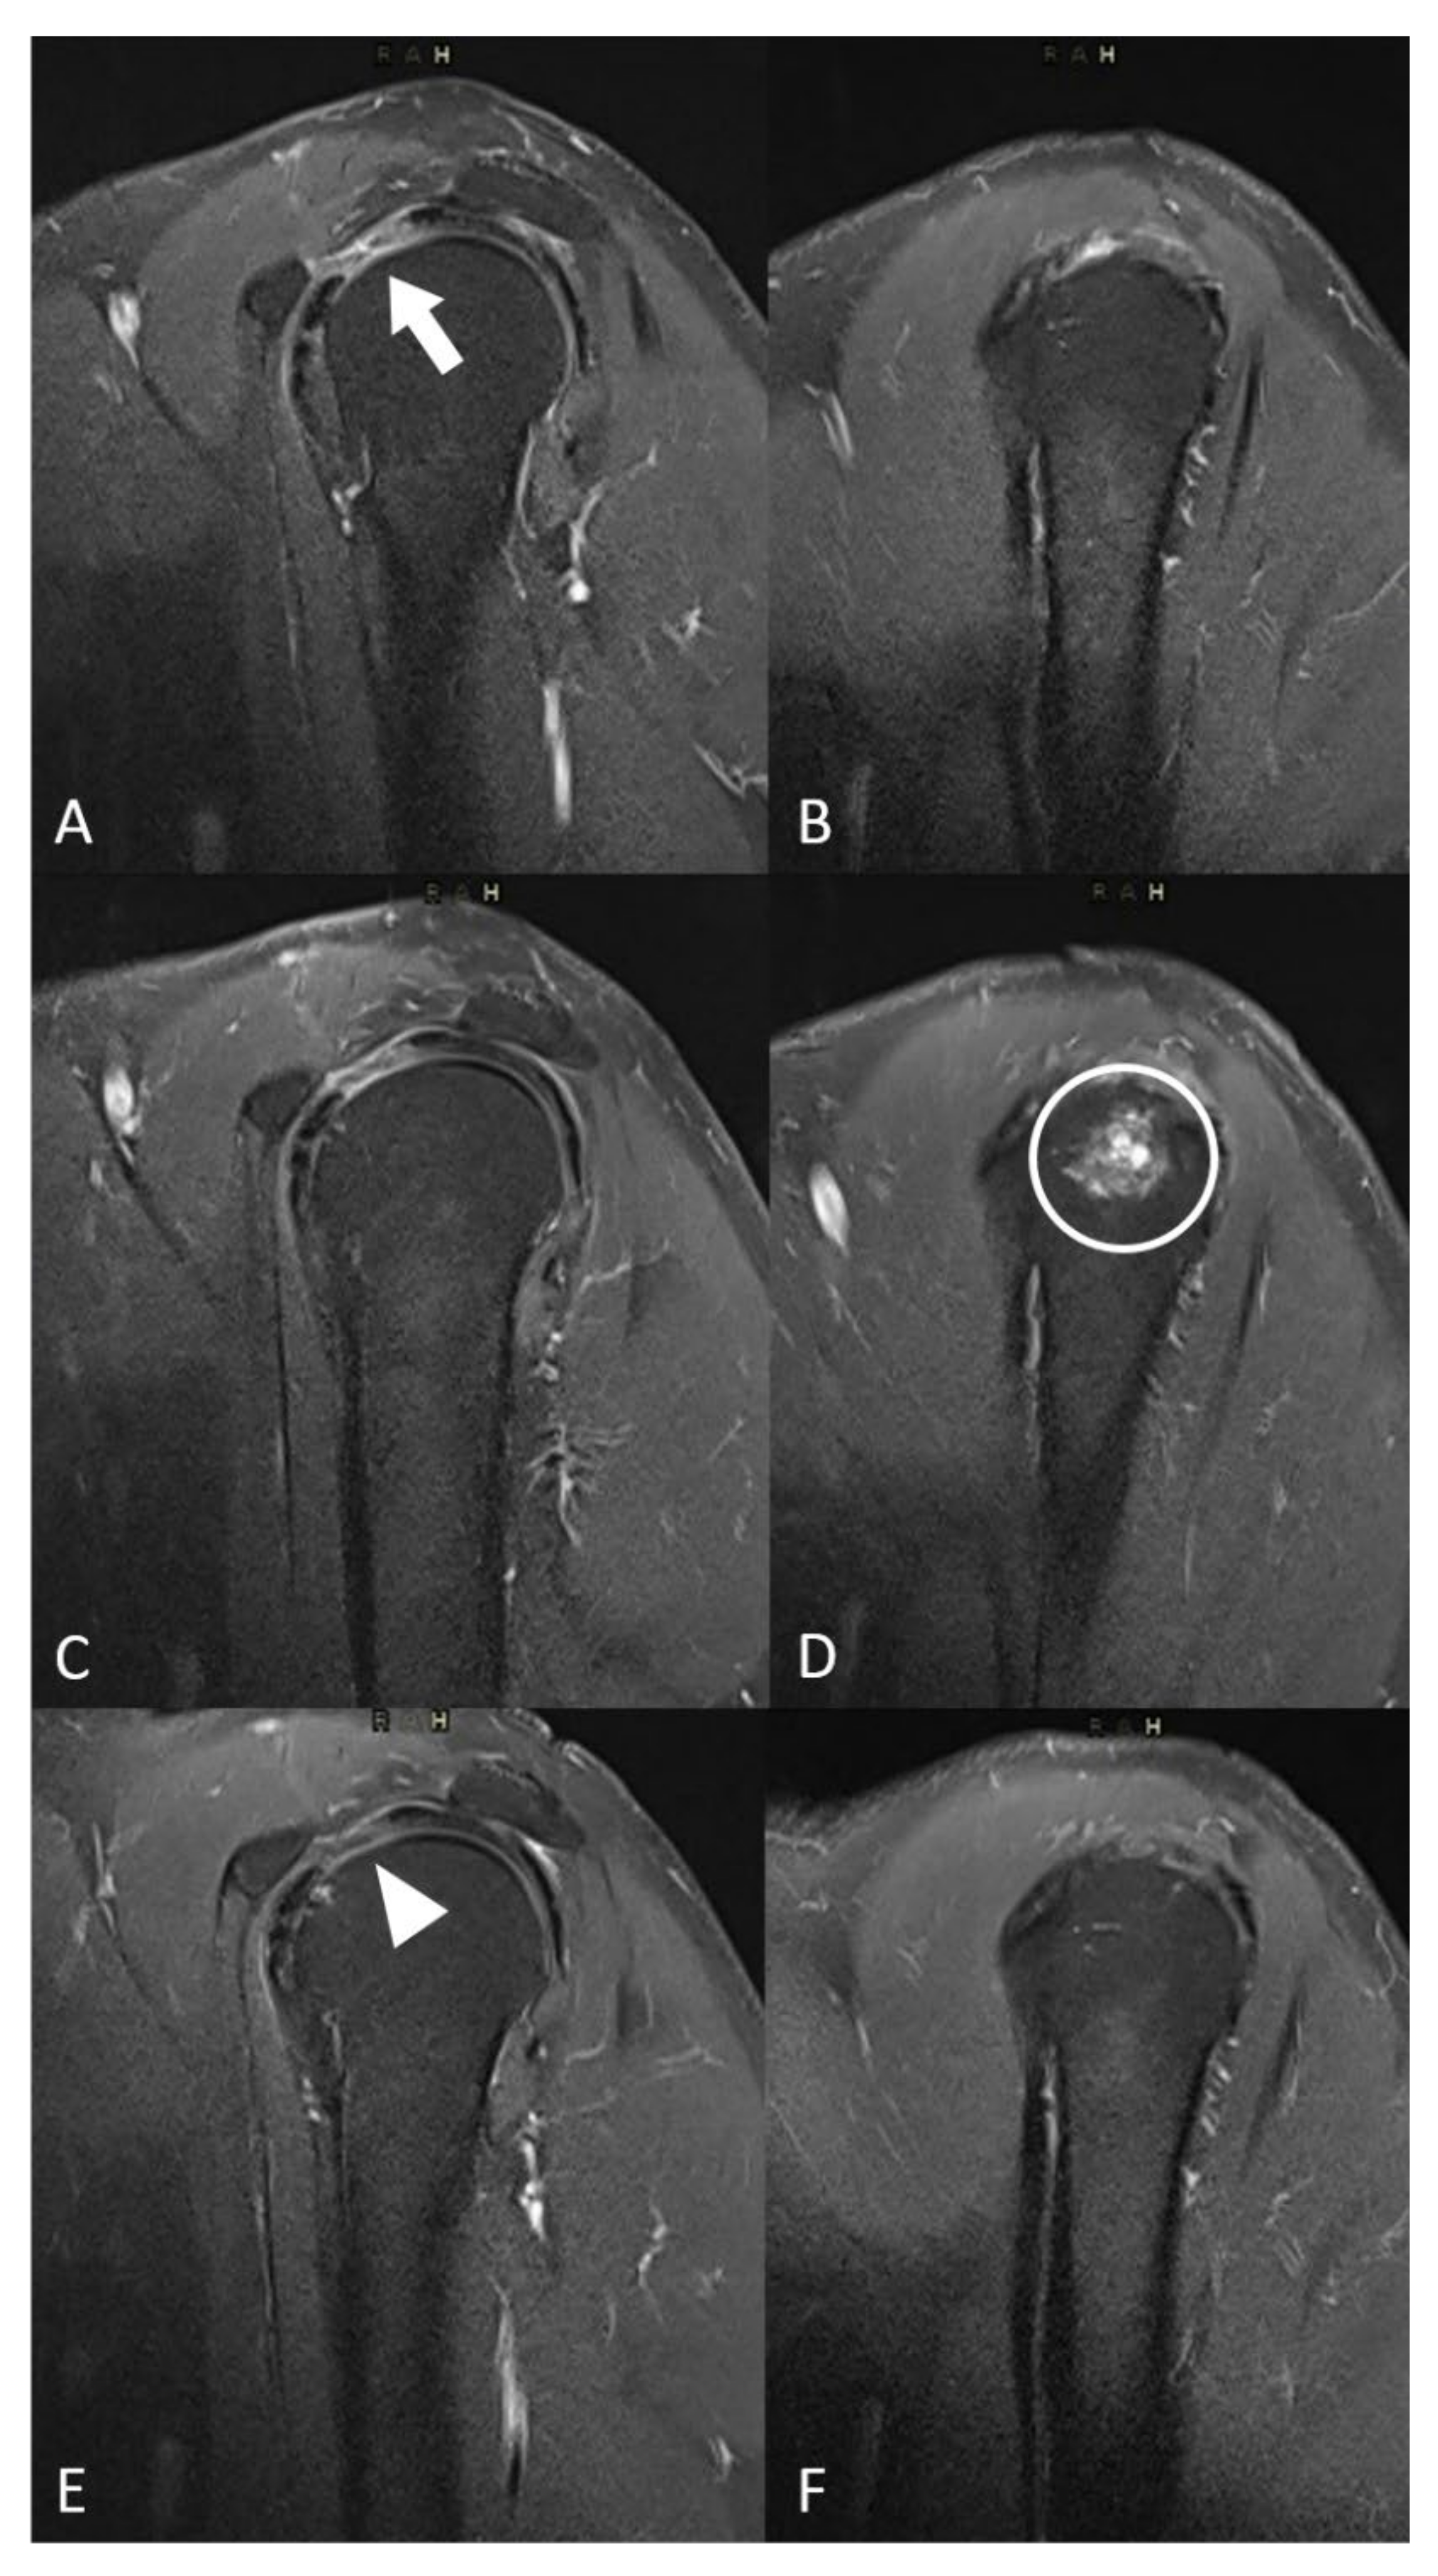

Figure 3. Evolution of MRI inflammatory signal and local complication. (A,B) Sagital T2 fat-sat MR images at baseline showed a hypersignal in the interval of rotator cuff (white arrow). (C,D) Sagital T2 fat-sat MR images one month after embolization showed a liquidian hypersignal in the humeral head (white circle) corresponding to focal oedema. (E,F) Sagital T2 fat-sat MR images 3 months after the procedure showed the decreased inflammatory signal in the interval of rotator cuff (white arrowhead) and the spontaneous disappearance of the humeral head edema.

3.4. Safety

Post-embolization syndrome, i.e., transient pain increase (around 10 days), was reported in eight patients (53%, Table 3). Two patients (13.3%) presented a moderate complication with transient skin ischemia managed with opioids and spontaneous recovery within 1 month. Three patients suffered from minor complications (transient paresthesia, n = 2 (13.3%)) and transient osteo-medullary edema (n = 1 (7.7%)) (Figure 3).

3.5. MRI Findings

Enhanced MR images before embolization were available for 13 patients (87%) and 1 patient had a non-enhanced MRI (including T2-weighted sequences) (Table 4). Angiographic blushes correlated with inflammatory signals on baseline MR images for 11 patients (85%). During the post-embolization period, 12 patients (80%) had enhanced MRI. A decrease in inflammatory abnormalities was reported on imaging in 9/12 patients (75%). The patient who presented osteo-medullary edema on MRI follow-up one month after embolization had spontaneous recovery, as shown on the 6-month control MRI with a decrease in the synovial inflammatory signal due to capsulitis (Figure 3).